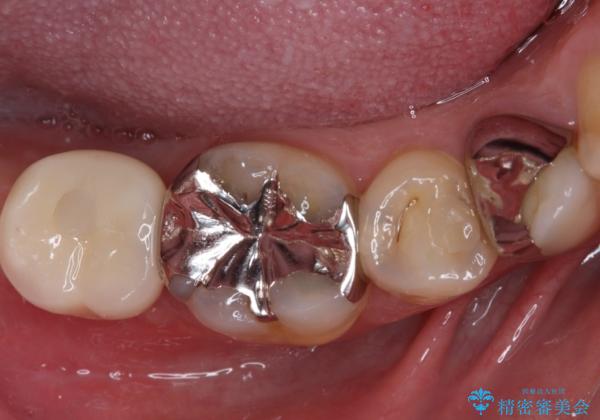

欠損と治療途中の奥歯 インプラント治療と補綴治療

- 下顎左右の奥歯を治療途中で放置してしまっているとのことで来院された患者様です。

欠損部はインプラントによる補綴治療を、土台の外れてしまった歯は、根管治療を行った上で、補綴治療を行うこととしました。